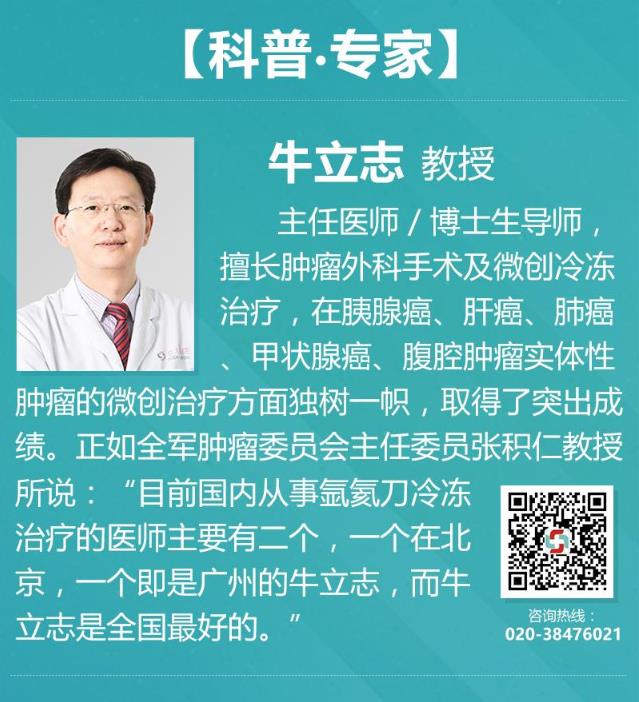

为了早一点治疗父亲的疾病,梭的儿子急忙的带着他在8月31号来到复大肿瘤医院。经过多次详细检查,诊断为:胰腺癌钩突部腺癌III期和2型糖尿病。肝、肺、甲状腺等多处出现结节,需要随后跟进治疗;牛立志博士与多名医生针对梭的病情展开讨论以及跟家属沟通后,分别在9月6号行“锁骨下静脉置管术”;9月7号行“胰腺肿瘤不可逆电穿孔术”。术后经过一系列的护理,梭的情况逐渐转好。

今天早上九点十五分,天气晴朗,牛立志博士和李红梅医生前脚后脚的踏入了602病房,走进去时候,一头橘红色卷发的梭盘坐在在床上,和身旁的家人有说有笑,看见牛博士和李医生到来,梭深感高兴。李医生说道:“74岁的尼泊尔ranten先生,胰腺癌纳米刀消融手术后一周,复查CT肿瘤完全坏死,肿瘤标志物CA199从术前的78降至正常。”

牛立志博士查阅梭的检查报告点了点头,翻阅梭的影像及化验情况不错,轻轻的拍着梭的肩膀耳旁说道“梭,告诉你一个好消息,你明天可以出院了。”梭激动的握住牛博士的手,把牛博士的手放在他的额头上,嘴里念叨着。正当牛博士表示疑惑看着他家属时,家属笑着解释道:“这是尼泊尔的一种礼节,是为了表示感谢牛博士。在来复大肿瘤医院之前,我们也曾咨询了印度等国家医生,他们都表示没有办法,来中国我们也是半信半疑,毕竟这么多医生都不肯接,没想到梭在进行纳米刀手术后,恢复那么快,症状也得到改善了,太感谢牛博士给予了我们一家生的希望。”

牛博士嘱咐道:“现在还不能掉以轻心,回去要记得按期做好化疗,局部晚期胰腺癌一定要做好全程管理,才能防止病情复发!”牛博士和梭一家合影留念。随后牛博士在网上查阅才得知“摸头礼”是国王对下属、臣民的礼节!这让牛博士大吃一惊,觉得这礼节有点重,其实能减轻患者的痛苦,就已经是给予复大医护人员最大的欣慰。